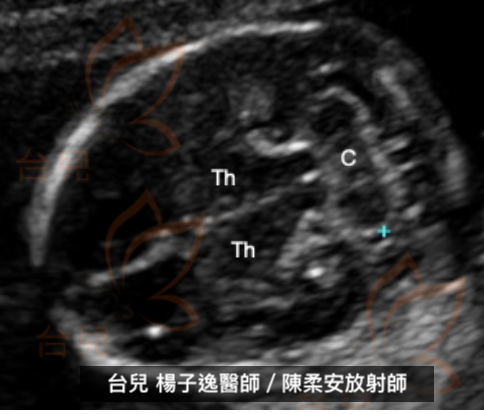

圖四:經小腦平面(Transcerebellar plane)(GA: 16+4 weeks)

C:小腦(Cerebellum),Th:丘腦(thalamic)(台兒診所提供臨床案例)